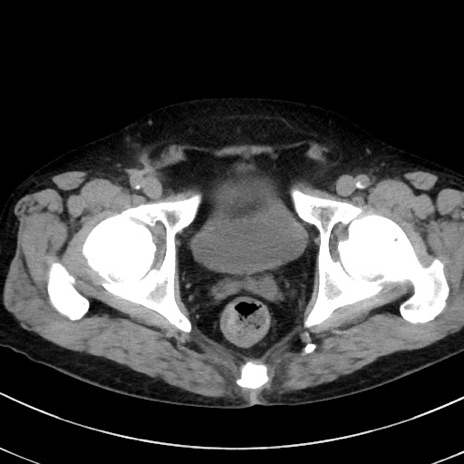

症例38(横断像)

【症例】70歳代 男性

【主訴】腹痛・嘔吐

【現病歴】昨晩より、嘔吐・腹痛あり。今朝になっても嘔吐あり。来院。

【既往歴】心臓バイパス手術、開腹胆摘、腸閉塞

【身体所見】BP 107/71mmHg、HR 116/min、腹部:平坦、軟、下腹部に軽度圧痛あり。反跳痛なし。

【データ】WBC 15100、CRP 0.32